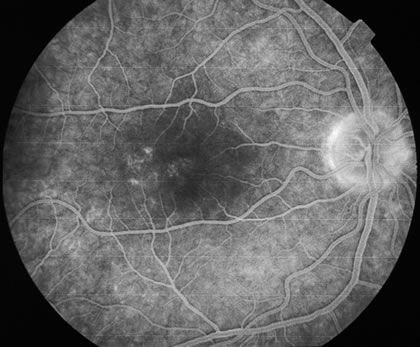

The classic findings in the acute cases are lesions of variable size that are hypofluorescent in the early phase of the fluorescein angiogram. In the late phases of the angiogram there is hyperfluorescence of the lesions. In the late phases, there also may be leakage from the disc as well, and there also may be staining of the retinal vessels because of the vasculitis. With resolution of the disease, there still may be a mottled pattern of fluorescence correlating with the areas of pigment clumping and pigment atrophy (Fig. 8).

Fig. 8. A. Early fundus angiogram showing hypofluorescence of the acute posterior multifocal placoid pigment epitheliopathy (APMPPE) lesions. B. Later stage of the angiogram showing staining of the APMPPE lesions.